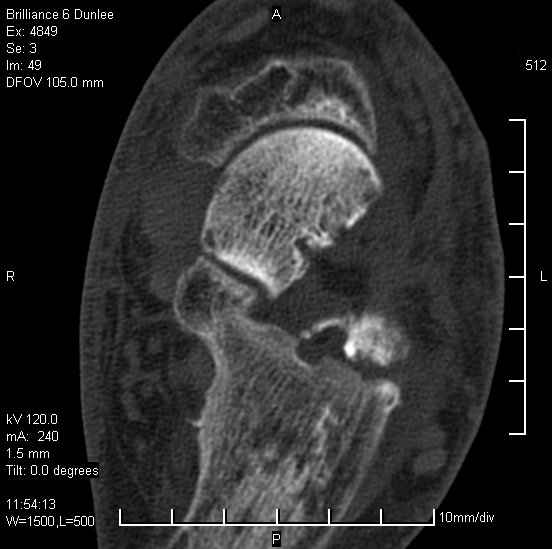

На лечении находится пациент 35 лет. Травма в сентябре 2008 г.- открытый вывих таранной кости

В день травмы ПХО, вправление вывиха, трансартикулярная фиксация. Рана зажила первично. С января нагрузка на конечность. С конца апреля- болевой синдром. На рентгенограммах и КТ признаки ас. некроза таранной кости, артроз подтаранного и голеностопного суставов.